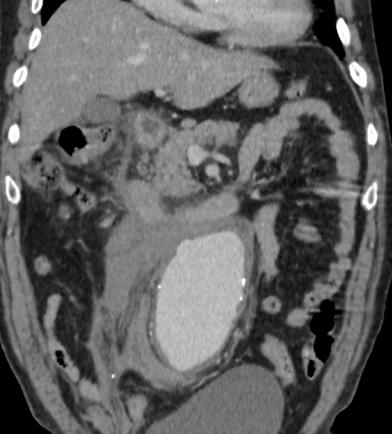

增强后:腹主动脉下段至左右髂总动脉上端明显扩张,最宽处约6.8cm,上下径约为13cm,成瘤样改变,边界清楚,形态规整。

1.腹主动脉瘤。(腹主动脉下段至左右髂总动脉上端)

3.右肾周及腹主动脉周围,中上腹腔见条带状及片状稍低密度影(多考虑腹腔包裹性积液,请结合临床病史。